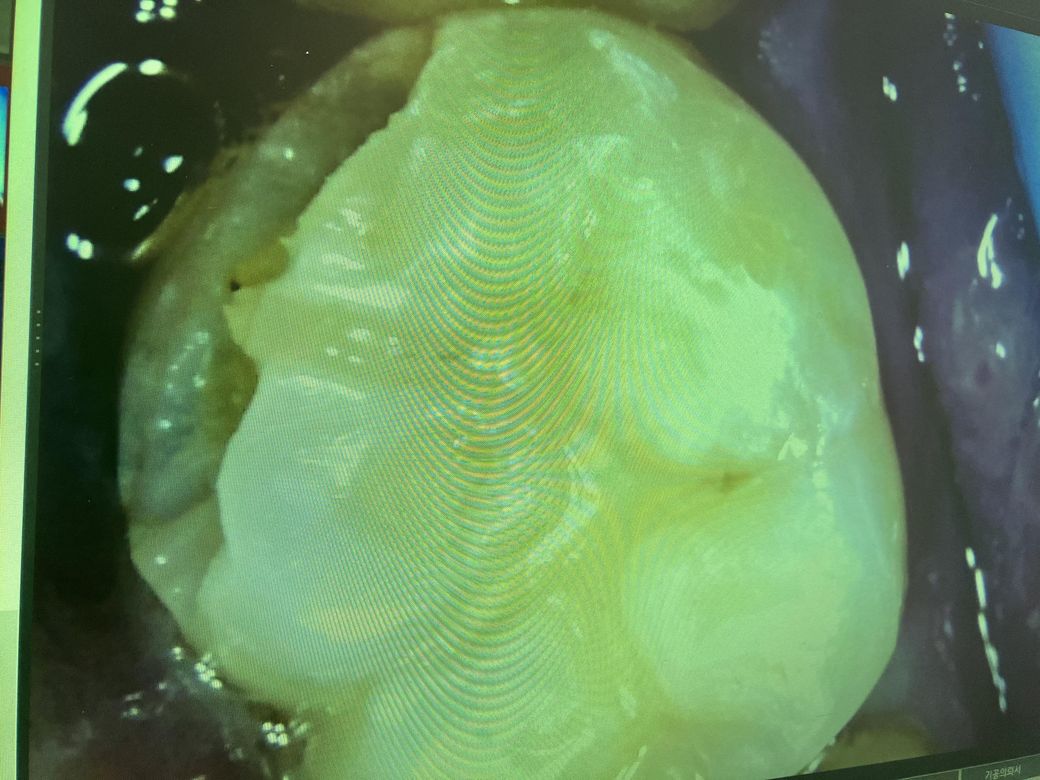

자르코니아? 크라운 작은어금니 하나 했습니다. 충치가 깊어서 크라운했습니다. 그런데 박고 7일있다 무슨 순살치킨먹다가 반으로 두동강나면서 옆에 큰어금니를 씹는바람에 큰어금니 위쪽도 조금 부셔졌어요 ... 너무 깊에 부셔진건 아니고 위에만 벗겨진거같은데 범랑질은 아닌거같아요 시리고 아픈거보니 그래서 내원을 햇는데 또 크라운을 권유하더라구요 .. 이건 인레이 레진으로 할수가없다고 생각보다 많이 깨진거라고 ... 쌩니를 그것도 어금니 두개나 이렇게 되서 이게 맞는건가 싶고 과잉진료가 아닌건가 싶기도하고 유튜브나 다른거보면 훨씬많이 부셔지고 해도 신경만 괜찮으면 레진이나 인레이로 때우던데 그렇게 심하게 부셔진것도아닌데 또 갈아서 임시치아 씌워놨네요 ... 도대체 뭘까요 ? 충치가 있어서 깨진게아니라 크라운이 떨어지면서 그걸 씹는바람에 깨진겁니다 . 말로는 옆면이고 이게 너무 오래되서 전체적으로 약해져있다.. 제가볼땐 전혀그런 느낌 그런걸 느끼질 못햇는데.. 도통 이해가 가질않네요 저번 같은곳에서 충치가 깊어 인레이를 했는데 그것보다 범위가 훨씬작은데 크라운이 왼말인가요..

• 1번 째 사진

저정도로 충치가 깨지셧다면 크라운을 하셔야될것같습니다. 상태에 따라서 신경치료도 하셔야될수도 잇을것같습니다.

사진으로만 봤을 경우에는 충치에 정확한 범위를 알기가 힘듭니다.

부분적으로 깨진 것 같아 보여도 치아 아래쪽에 충치가 많이 진행되어 있다면 인레이 등으로 치료하는 것이 힘들 수 있습니다 자세한 확인을 위해서 치과에서 진료를 받아 보는 것이 좋습니다